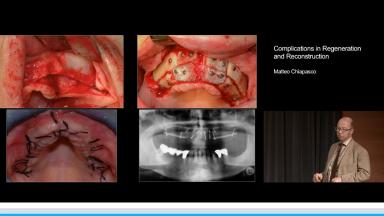

Complications in Regeneration and Reconstruction

This lecture reviews in detail the various defects encountered in clinical practice that may need regenerative procedures for hard and soft tissue augmentation. The presentation is supported with excellent visual aids that illustrate how these defects can be reconstructed for prosthodontically driven implant placement. It also addresses how to prevent complications in regenerative and reconstruction procedures as well as the predominant treatment options to manage these complications. Clinical outcomes are supported by reference to several studies and clinical recommendations from the 4th ITI Consensus Conference.